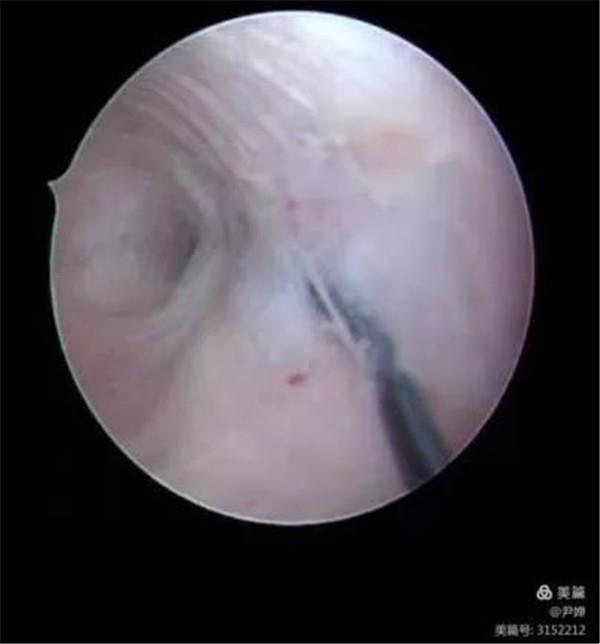

51歲的李大姐,前一段時間來我院取環(huán),環(huán)已經(jīng)上了20年,15年前有同房痛于是基本不同房了,最近一直小肚子隱隱痛于是來醫(yī)院檢查。超聲發(fā)現(xiàn)她的愛母環(huán)位置移位,一個端點嵌頓在子宮前壁,一個端點嵌頓在宮頸前唇,婦科醫(yī)生通過宮腔鏡把環(huán)取出來,電話回訪李大姐很是感謝,不痛了也能同房了。

節(jié)育器嵌頓

由于節(jié)育器過大或置放時操作不當(dāng)損傷宮壁,導(dǎo)致部分或全部節(jié)育器嵌入子宮肌層內(nèi),為節(jié)育器嵌頓。聲像表現(xiàn) 節(jié)育器偏離宮腔中心部位,嵌入肌層或接近漿膜層。對臨床取環(huán)失敗、可疑節(jié)育器嵌頓時,可行經(jīng)陰道掃查,還可行三維超聲成像,能更清楚地顯示節(jié)育器嵌頓的程度和部位,以便制定合適的取環(huán)手術(shù)途徑。